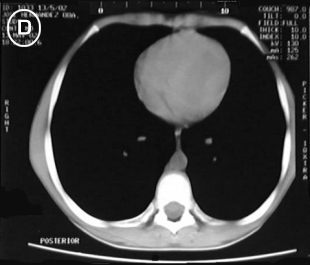

Tomografia A Tomografia B

Estudio tomografico milimetrico, progresivo desde el vértice hasta bases pulmonares, en donde no se apreciaron procesos pleuro-parenquimatosos; Mediastino sin adenopatías; En los cortes pretraqueales (A) y (B) se aprecia imagen de densidad de partes blandas en correlacion con probable timo hiperplasico y/o timoma, extendiendose distalmente anterior a los grandes vasos (C), observese su ausencia en el corte precordial inferior (D), donde apreciamos una silueta cardiaca de morfologia conservada, las bases pulmonares y el hemi-abdomen superior no mostraron alteraciones.

Tomografia C Tomografia D